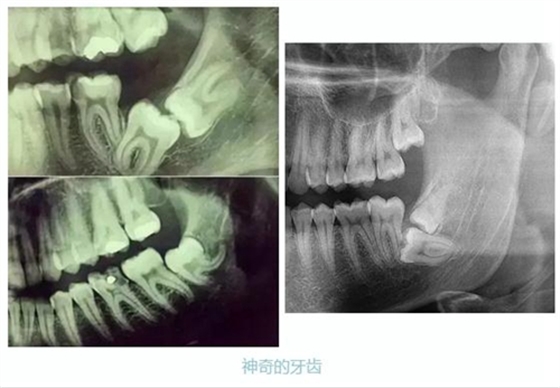

先放幾張圖,讓你們漲漲姿勢(shì),不拍片根本不知道你的牙齒長(zhǎng)得會(huì)有多奇葩!

從上圖中可以知道除了外層的一點(diǎn)牙釉質(zhì),牙齒里面出了問(wèn)題,肉眼是無(wú)法觀察到的。牙醫(yī)不長(zhǎng)透視眼當(dāng)然不能透過(guò)現(xiàn)象看到牙齒本質(zhì)嘍。因此,為了對(duì)牙齒進(jìn)行全面的了解,拍個(gè)牙片還是很有必要的。

牙齒的牙根是埋在牙槽骨中的,醫(yī)生沒(méi)有透視眼,為了解患牙的牙根的形態(tài)、走向、長(zhǎng)度及根尖周有無(wú)病變及病變大小,或者懷疑有肉眼無(wú)法確認(rèn)的其它牙科問(wèn)題,都會(huì)建議患者去牙科的X光,甚至,口腔CT來(lái)全面性地確認(rèn)問(wèn)題,以訂定合適的治療計(jì)劃。